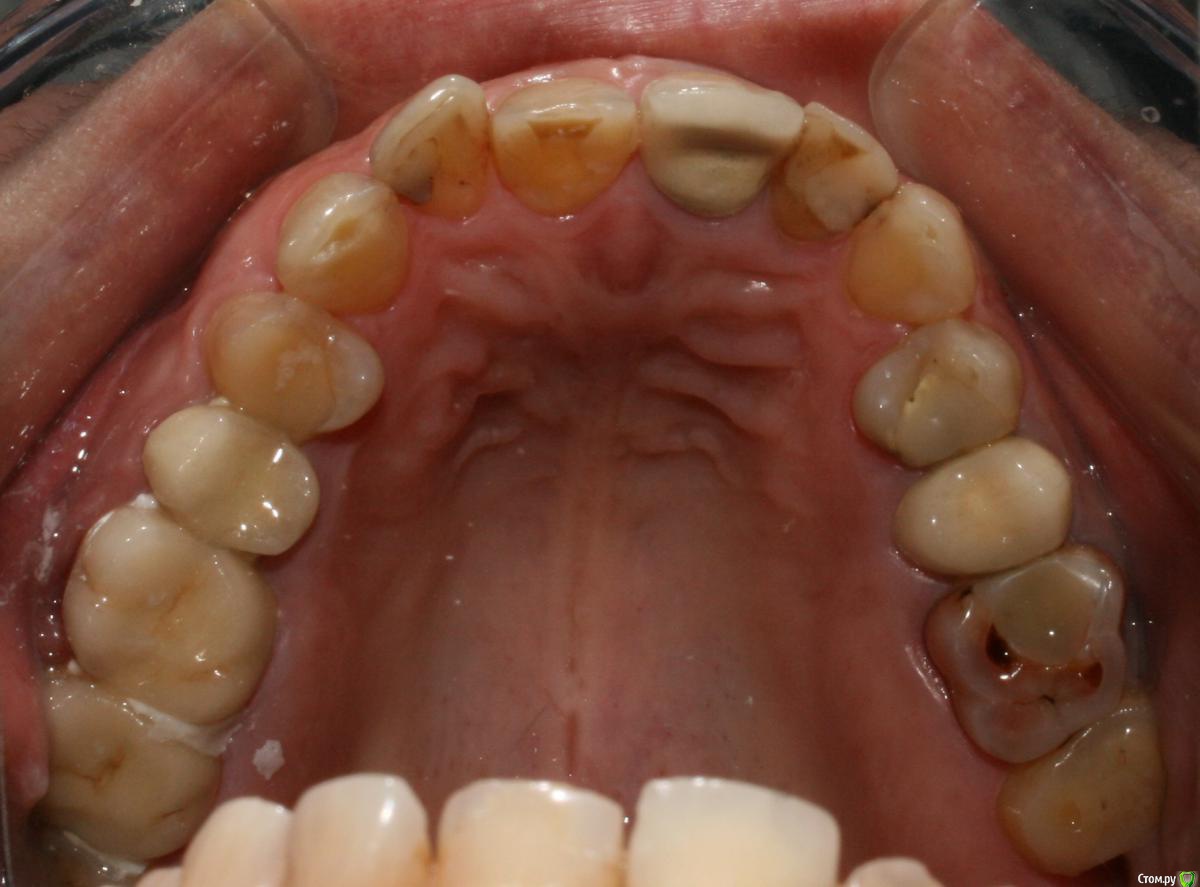

kramer Опубликовано 17 января, 2018 Поделиться Опубликовано 17 января, 2018 (изменено) Коллеги, добрый вечер. Помогите начинающему ортопеду. Заранее прошу простить за качество фото. Пациентка обратилась с целью улучшения эстетики фронтальных зубов. Около года назад один врач из нашей клиники делал м/к на боковые зубы (пациентку устраивают), при этом, по всей видимости, было снижение прикуса из-за стирания, но его высоту не восстанавливали. Теперь настало время передних зубов, и работать, получается, придется с имеющейся высотой. План лечения: 14, 24 - м/к, 13-23 имакс коронки/виниры. Меня смущают фасетки стираемости на клыках в/ч. Вопрос: каким образом лучше их реставрировать во избежание сколов реставраций? Делать полные коронки? Спасибо, надеюсь на ваш совет. Изменено 17 января, 2018 пользователем kramer Ссылка на комментарий

krokomot Опубликовано 17 января, 2018 Поделиться Опубликовано 17 января, 2018 Просится тотал, в случае, лайт варианта делайте все имах, везде показаны коронки, хотябы 3\4. Интересная концепция с зубом 1.1))) Ссылка на комментарий

krokomot Опубликовано 18 января, 2018 Поделиться Опубликовано 18 января, 2018 Спасибо. 11 сделан в каких-то махровых годах. Вариант с винирами отпадает по функциональным или эстетическим причинам?По объему сохранившихся тканей у зубов Ссылка на комментарий

StomV Опубликовано 22 января, 2018 Поделиться Опубликовано 22 января, 2018 Я не пойму,почему все в один голос твердят,что здесь нужно поднимать прикус?Какие показания? С чего вы это решили?Нужно исходить из возраста пациента. Да здесь видны фасетки стираемости,но не стоит забывать,что есть еще компенсация стираемости в виде роста альвеолярного отростка с зубами (гипертрофия) и далеко не всегда стираемость приводит к снижению МАВ. Здесь как раз намного важнее определиться с ЦС и ВНЧС,как минимум провести тесты,сделать КТ сустава.Если все в норме,то нет нужны поднимать высоту. Я думаю в данной клинической ситуации возможно отмоделировать достточно неплохо фронт,хотелось бы увидеть ваш вариант воска. 1 Ссылка на комментарий